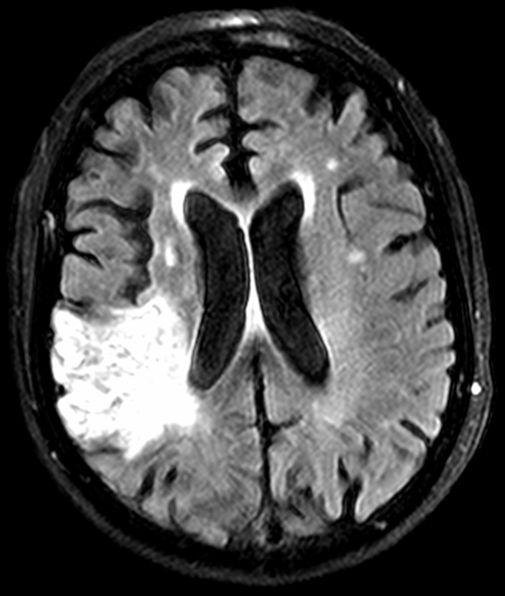

Magnetic Resonance Imaging

(MRI)

- Uses a magnetic field and pulses of radio wave energy to make pictures

- Used to detect tumors, bleeding, injury, blood vessel disease, or infection

- The best tool to detect a stroke

- Most expensive imaging study

- Must remove all metal prior to exam